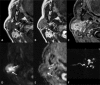

Inflammatory and obstructive disorders of the salivary glands are caused by very different pathological conditions affecting the gland tissue and/or the excretory system. The clinical setting is essential to address the appropriate diagnostic imaging work-up. According to history and physical examination, four main clinical scenarios can be recognised: (1) acute generalised swelling of major salivary glands; (2) acute swelling of a single major salivary gland; (3) chronic generalised swelling of major salivary glands, associated or not with "dry mouth"; (4) chronic or prolonged swelling of a single major salivary gland. The algorithm for imaging salivary glands depends on the scenario with which the patient presents to the clinician. Imaging is essential to confirm clinical diagnosis, define the extent of the disease and identify complications. Imaging techniques include ultrasound (US), computed tomography (CT) and magnetic resonance (MR) with MR sialography.